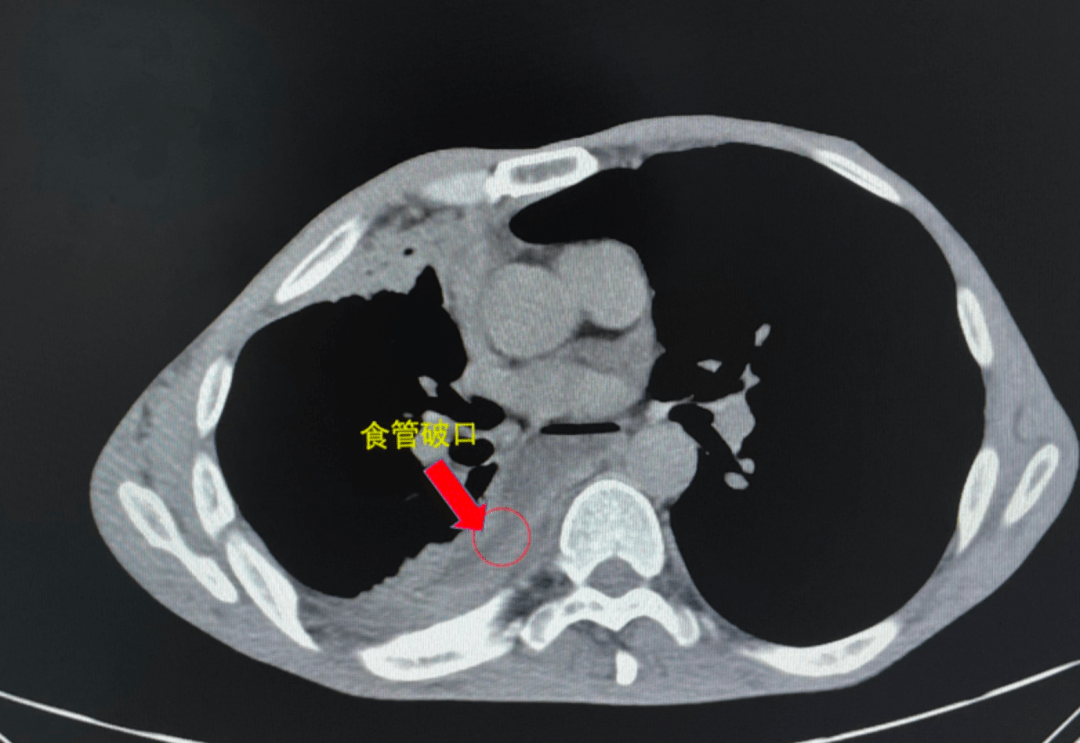

ct示:食管异物!

图片尺寸3022x4030